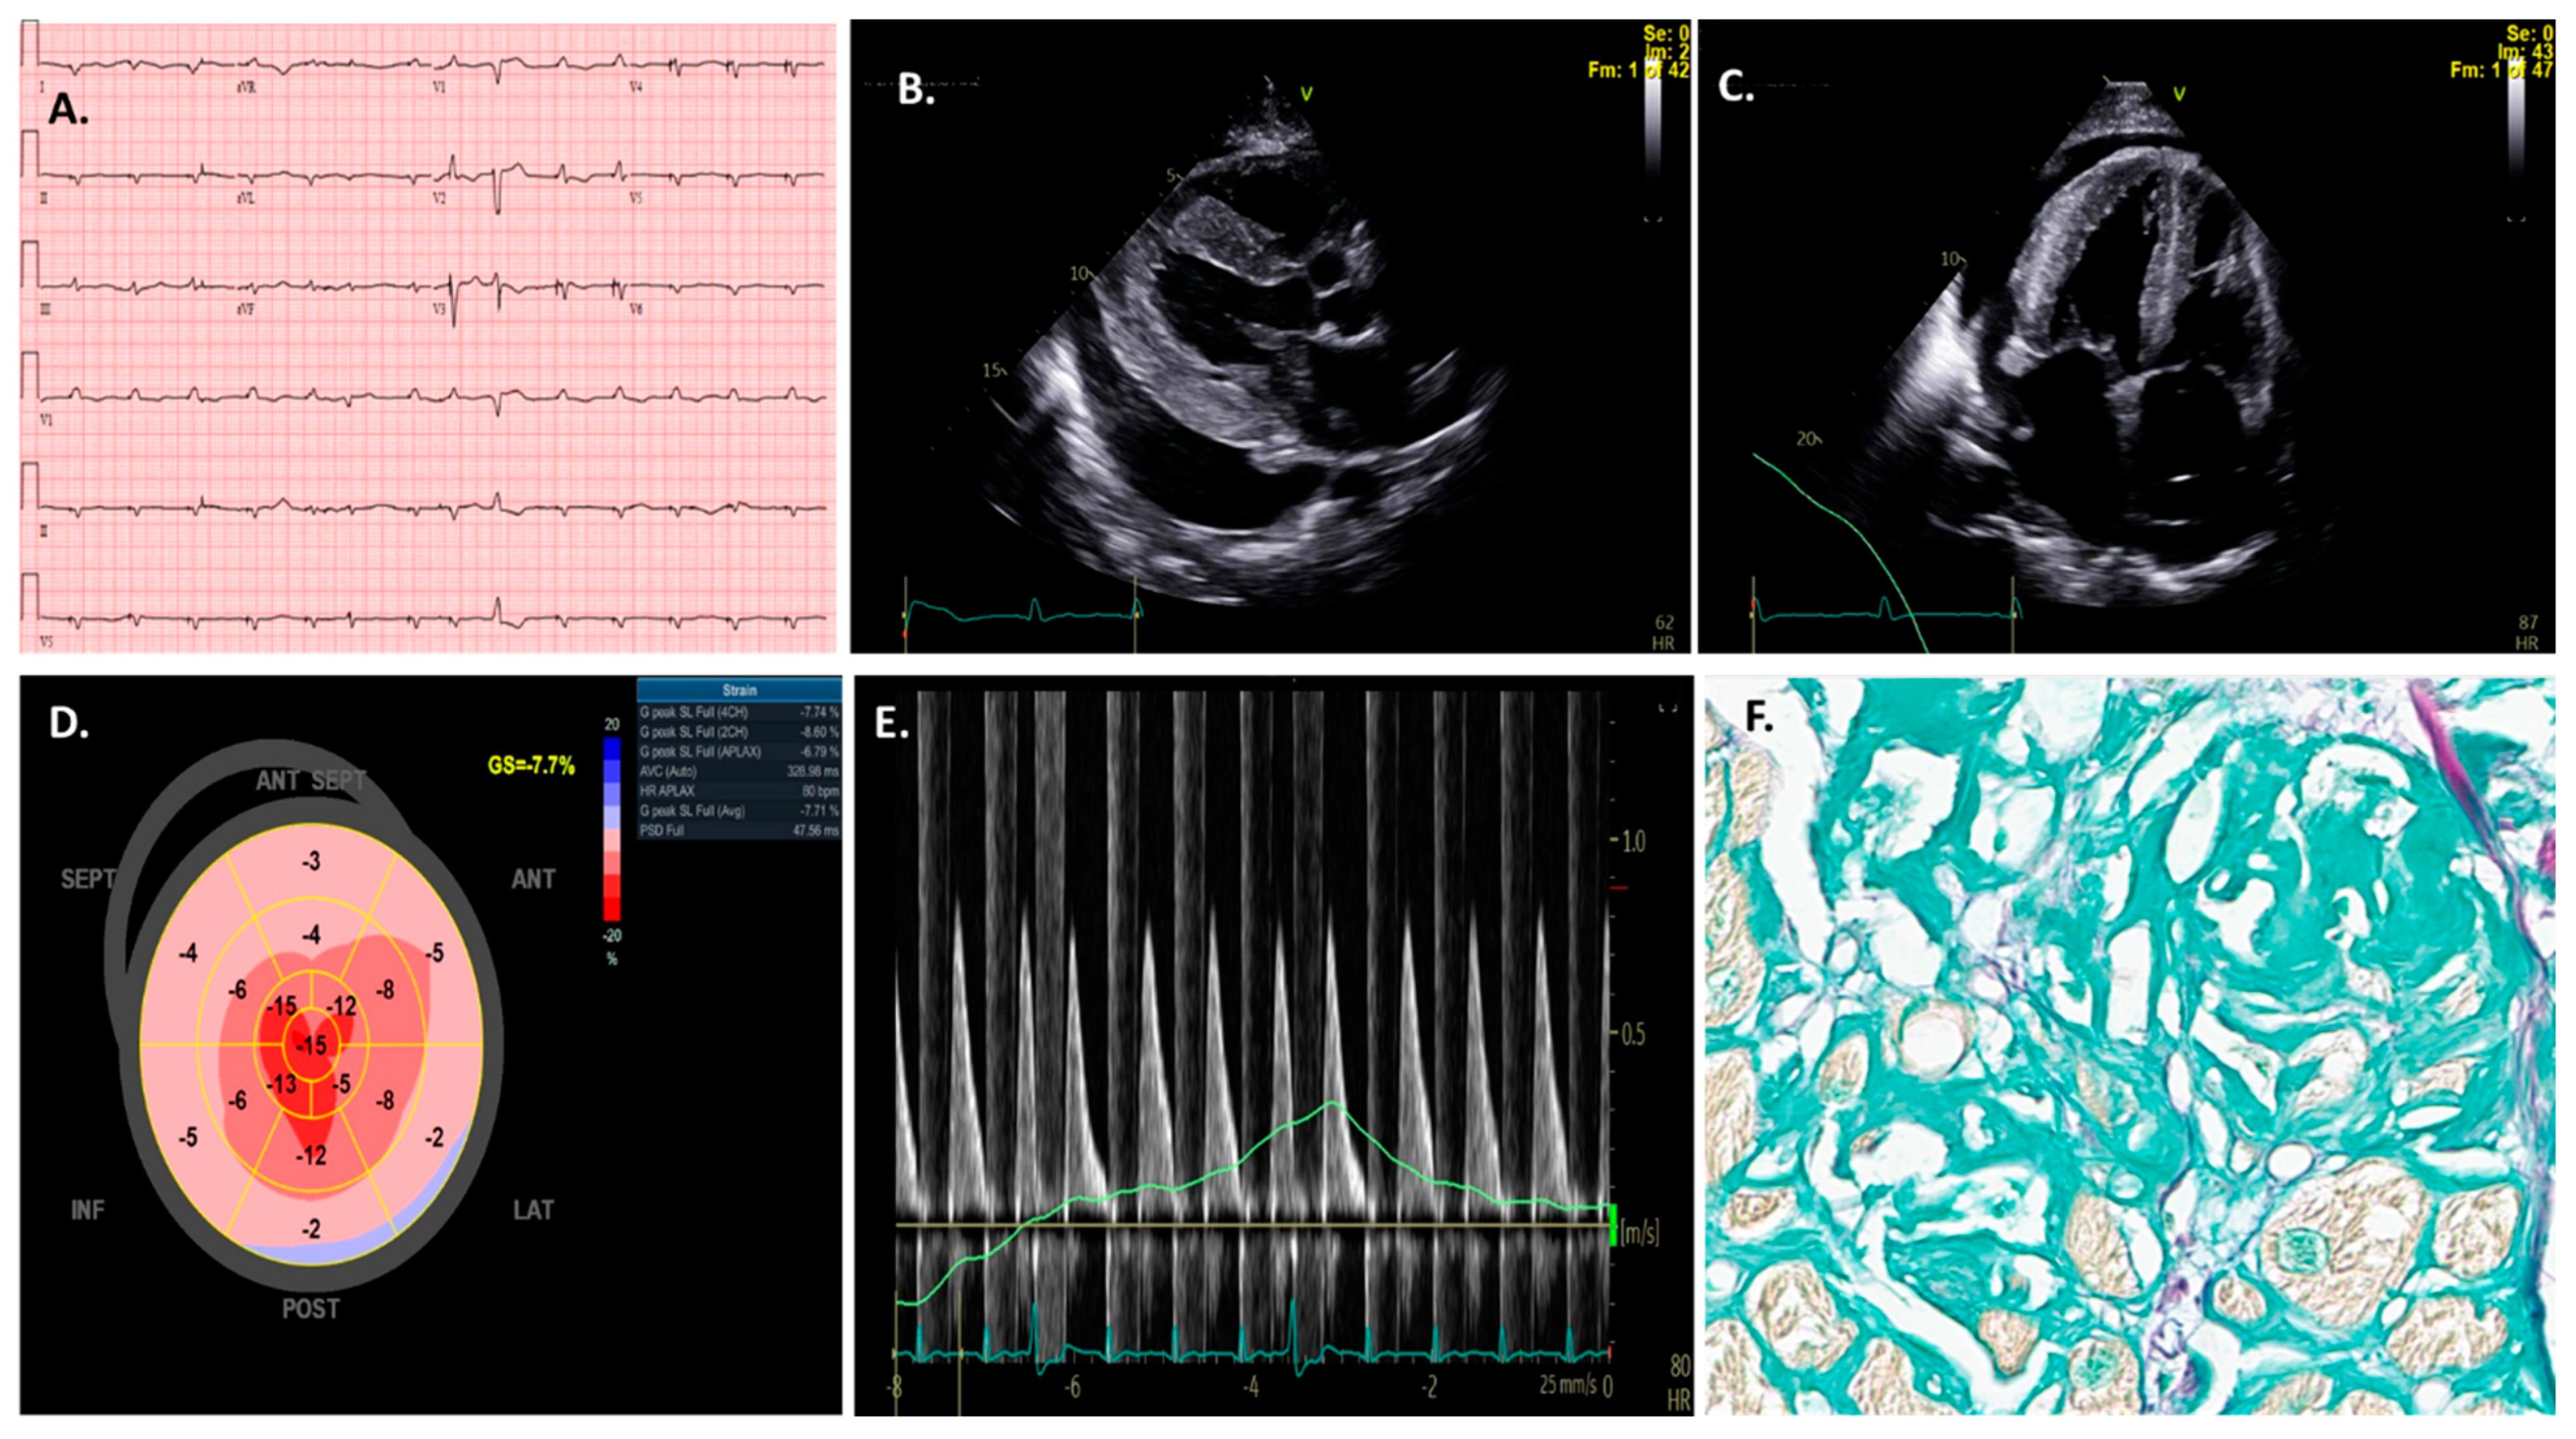

2. AI Applications to Electrocardiogram (ECG) in Cardiac Amyloidosis

The electrocardiogram (ECG) remains the first-line and most widely utilized test for cardiac assessment (Figure 3A) [15,16]. ECG changes in CA reflect the multifaceted nature of this disease process [17], including myocardial infiltration, fibrosis, and conduction system dysfunction [18]. Arrhythmias and severe conduction abnormalities are prevalent in patients with CA, present in up to 40% of cases [19], with atrial fibrillation (AF) being the most frequent arrhythmia [20].

Echocardiography is generally the initial imaging test for investigating CA (Figure 3B–E) [30]. Extensive previous research has demonstrated the diagnostic and prognostic value of two-dimensional (2D) and Doppler echocardiography for the initial identification of CA [31]. Overall, echocardiographic findings of unexplained increased ventricular wall thickness should raise suspicion of CA when in elderly patients or patients with a family or personal history of amyloidosis. Other hallmark changes may include a small left-ventricular (LV) cavity, valve thickening, bi-atrial enlargement in the setting of restrictive physiology, variable presence of a pericardial effusion, and abnormal global longitudinal strain [10,32,33].

A reduced global longitudinal strain (GLS) with relative apical sparing is a specific pattern that is pathognomic for CA and correlates with poor outcomes [18,30,34,35,36,37,38,39,40]. An apical sparing pattern on the strain was found to have a high sensitivity of 93% and specificity of 82% in differentiating CA from other cardiomyopathies with increased wall thickness [41,42]. However, echocardiographic changes may be subtle early in the disease process or may occur with coexisting processes such as hypertension (HTN) or end-stage renal disease (ESRD), and as such are not specific or definitive for CA. Additionally, with regard to strain measurement, the manual contouring of the LV endocardium may result in significant intra- and inter-operator variability that may affect the accuracy of echocardiography in diagnosing CA patients [31,43]. Furthermore, GLS assessment in patients with atrial fibrillation (AF), which is very common among CA patients, is challenging because of the irregular and variable heart rate [44], which affects the timing and duration of the cardiac cycle. As such, research aimed at the use of AI algorithms for the detection of CA using echocardiography may help identify the disease earlier and help reduce observer variability [31,45].

Clinical and imaging suspicion usually prompt further targeted evaluation for CA. Pathology-related tests, including tissue biopsy (from bone marrow, fat pad, or endomyocardial (Figure 3F)), and serum studies such as monoclonal protein detection (e.g., urine protein immunofixation or serum free light chain ratio analysis) can be used where appropriate for a more definitive diagnosis. Furthermore, laser microdissection with mass spectrometry may provide additional information for subtype analysis differentiating ATTR-CA from AL-CA [73,74]. Significantly, pathology may exclude rare forms of amyloidosis, such as AApoA-1 and AApoA-4 amyloidosis, which is essential for the treatment choice [3,75,76]. However, many of these pathological techniques depend mainly on subjective data interpretation by expert pathologists or may be limited by low diagnostic accuracy (e.g., immunohistochemistry) [77,78]. In addition, tissue acquisition, processing, and interpretation require experience and at unexperienced centers misinterpretation of data can occur. Therefore, utilizing AI models may help decrease observer variability and allow for increased accuracy in pathological evaluation.

Figure 3. Traditional electrocardiogram (ECG) findings (A) in a patient with cardiac amyloidosis; note the low-voltage complexes with increased left-ventricular wall thickness on echocardiography (B,C). (D) depicts the traditional Bull’s-Eye graph of this disease; the apical longitudinal strain is preserved, but there is a substantial decrease in basal and medial segments. (E) shows another typical echocardiography feature of cardiac amyloidosis patients such as diastolic dysfunction. All the prior findings are critical for the diagnosis of this disease; however, confirmatory tests are needed following clinical suspicion. In this specific case, an endomyocardial biopsy (F) confirmed the diagnosis.